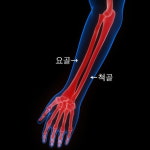

요골 지도 이미지

요골